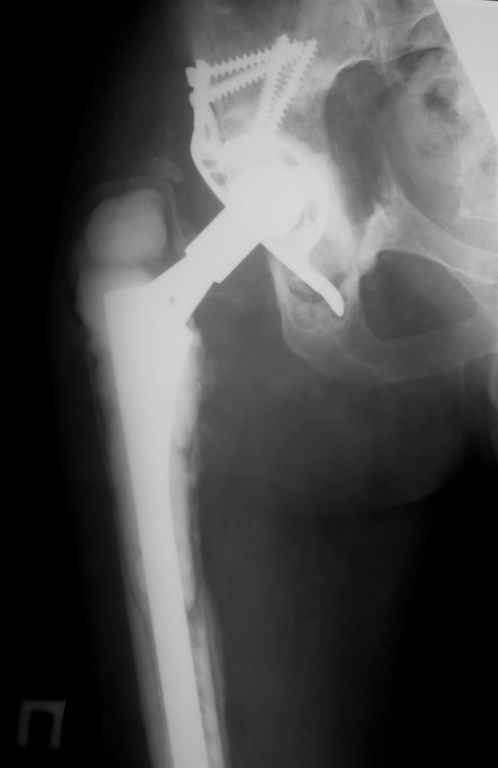

Апрель 2005 |  Декабрь 2005 |  Декабрь 2005 | Реревизия по поводу нестабильности вертлужногокомпонента была выполнена в апреле 2005 г. с пересадкой вертлужной впадины (аллотрансплантат)и защитой трансплантата кольцом Б-Ш.Нагноение выявлено через 6 месяцев, был полностью удален эндопротез (и вертлужный и бедренный компоненты), тщательная ХО мягких тканей с установкой подготовленной из цемента с антибиотиками (родной гентамицин + насыпной ванкомицин) вертлужной впадины опять же на цемент. Установлена новая ножка взамен удаленной на к/цемет с антибиотиками. Рана зажила, б-ая выписана домой. По этой методике прооперировано четверо б-х, пока без рецидива инфекции, одна из пациенток уже поступила для второго этапа.С уважением, Р.Тихилов

Мы установили временный протез предназначенный только для движений и ходьбы без нагрузки. "Старый" цемент мы не удаляли поэтому спустя 3-4 месяца планируется выполнить расширенную остеотомию бедра с удалением всего к/цемента и установкой ножки бесцементной фиксации. Обязательным условием является хорошая дистальная фиксация на протяжении минимум 6-8 см. Скорее всего мы используем изогнутую ножку длиной 254 мм, это будет либо ZMR, либо Solution, я еще не планировал этот этап операции.